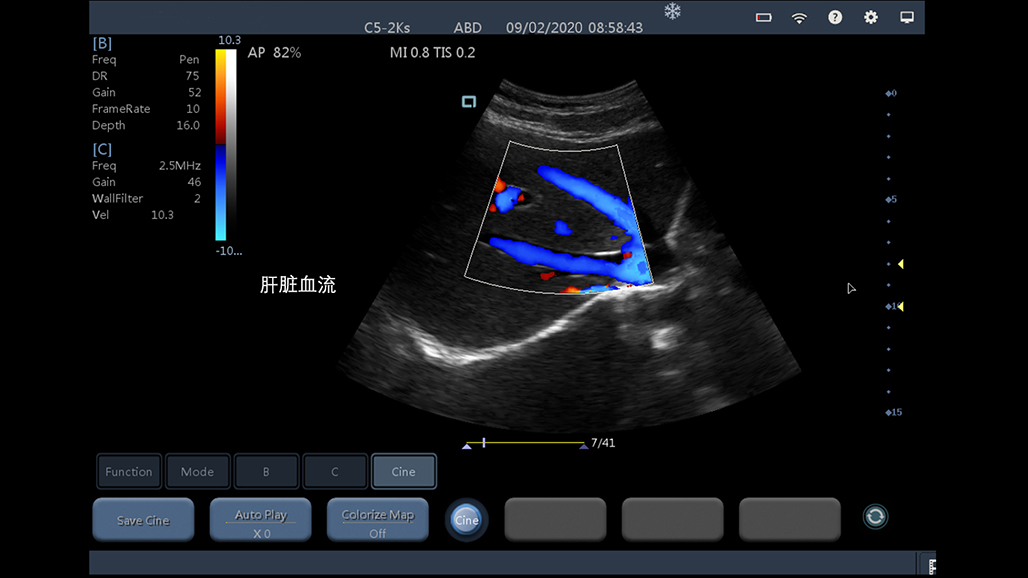

腹部

肾脏